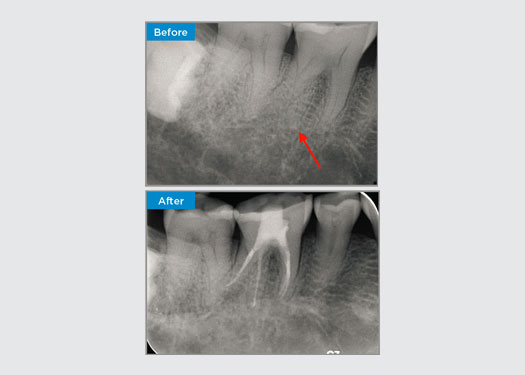

El paciente presentaba periodontitis apical asintomática en el diente 34. En la radiografía preoperatoria, se observó el diente 34 con dos raíces visibles. Sin embargo, los datos del CBCT confirmaron un premolar de tres raíces y los canales divididos en tres en la raíz media. Una selección cuidadosa de la lima es fundamental para este diente delicado.

Dr. Jack Lin, endodoncista, Sídney, Nueva Gales del Sur, Australia

En esta situación, la preservación de la estructura del diente y la raíz es esencial para reducir el riesgo de desplazamiento, transporte, compresión, perforación y fractura de la raíz. La selección de casos, el diagnóstico y la planificación previa al tratamiento son muy importantes. Es fundamental la selección de limas de endodoncia con flexibilidad, eficiencia y respeto por la anatomía natural de la raíz.